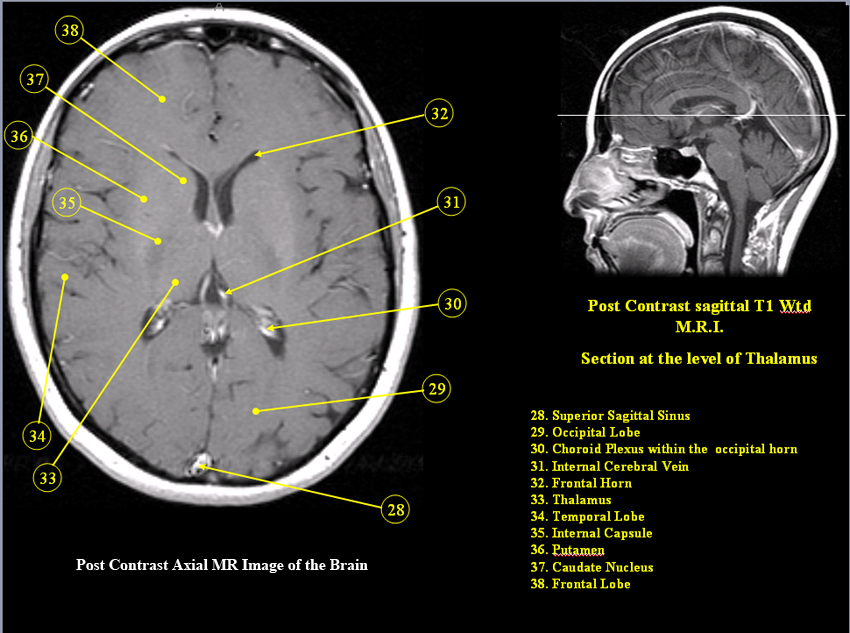

MR Brain and Spine